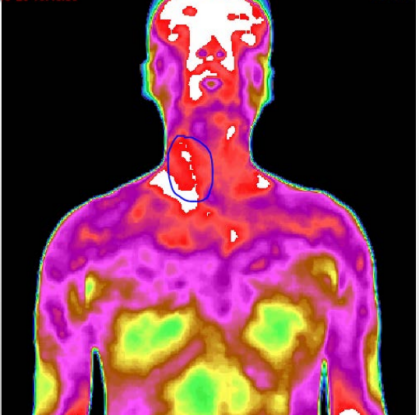

近期,广东省第二人民医院(以下简称“省二医”)疼痛科引入了红外热像检查系统,能够快速准确探测到目标物的温度变化情况,并将其转化为温度值图像,再通过专业的图像分析工具,帮患者把疼痛感受客观“描述”出来,在不接触、无辐射的情况下使疼痛形象化,大大提高诊断的准确率和治疗的有效率!

4.高敏感度:能极其敏感地接收人体细胞新陈代谢所产生的热辐射(小于0.025 ℃ ),显示人体内异常热源的分布、深度、强度、形态及走势;

5.精准度高:数据表明,红外热像对早期恶性肿瘤的诊断准确率已达81%,对早期心梗、脑出血、栓塞可提出准确论断和预示,其准确率超过85%,对甲状腺、乳腺、前列腺和妇科疾病的诊断准确率超过90%。